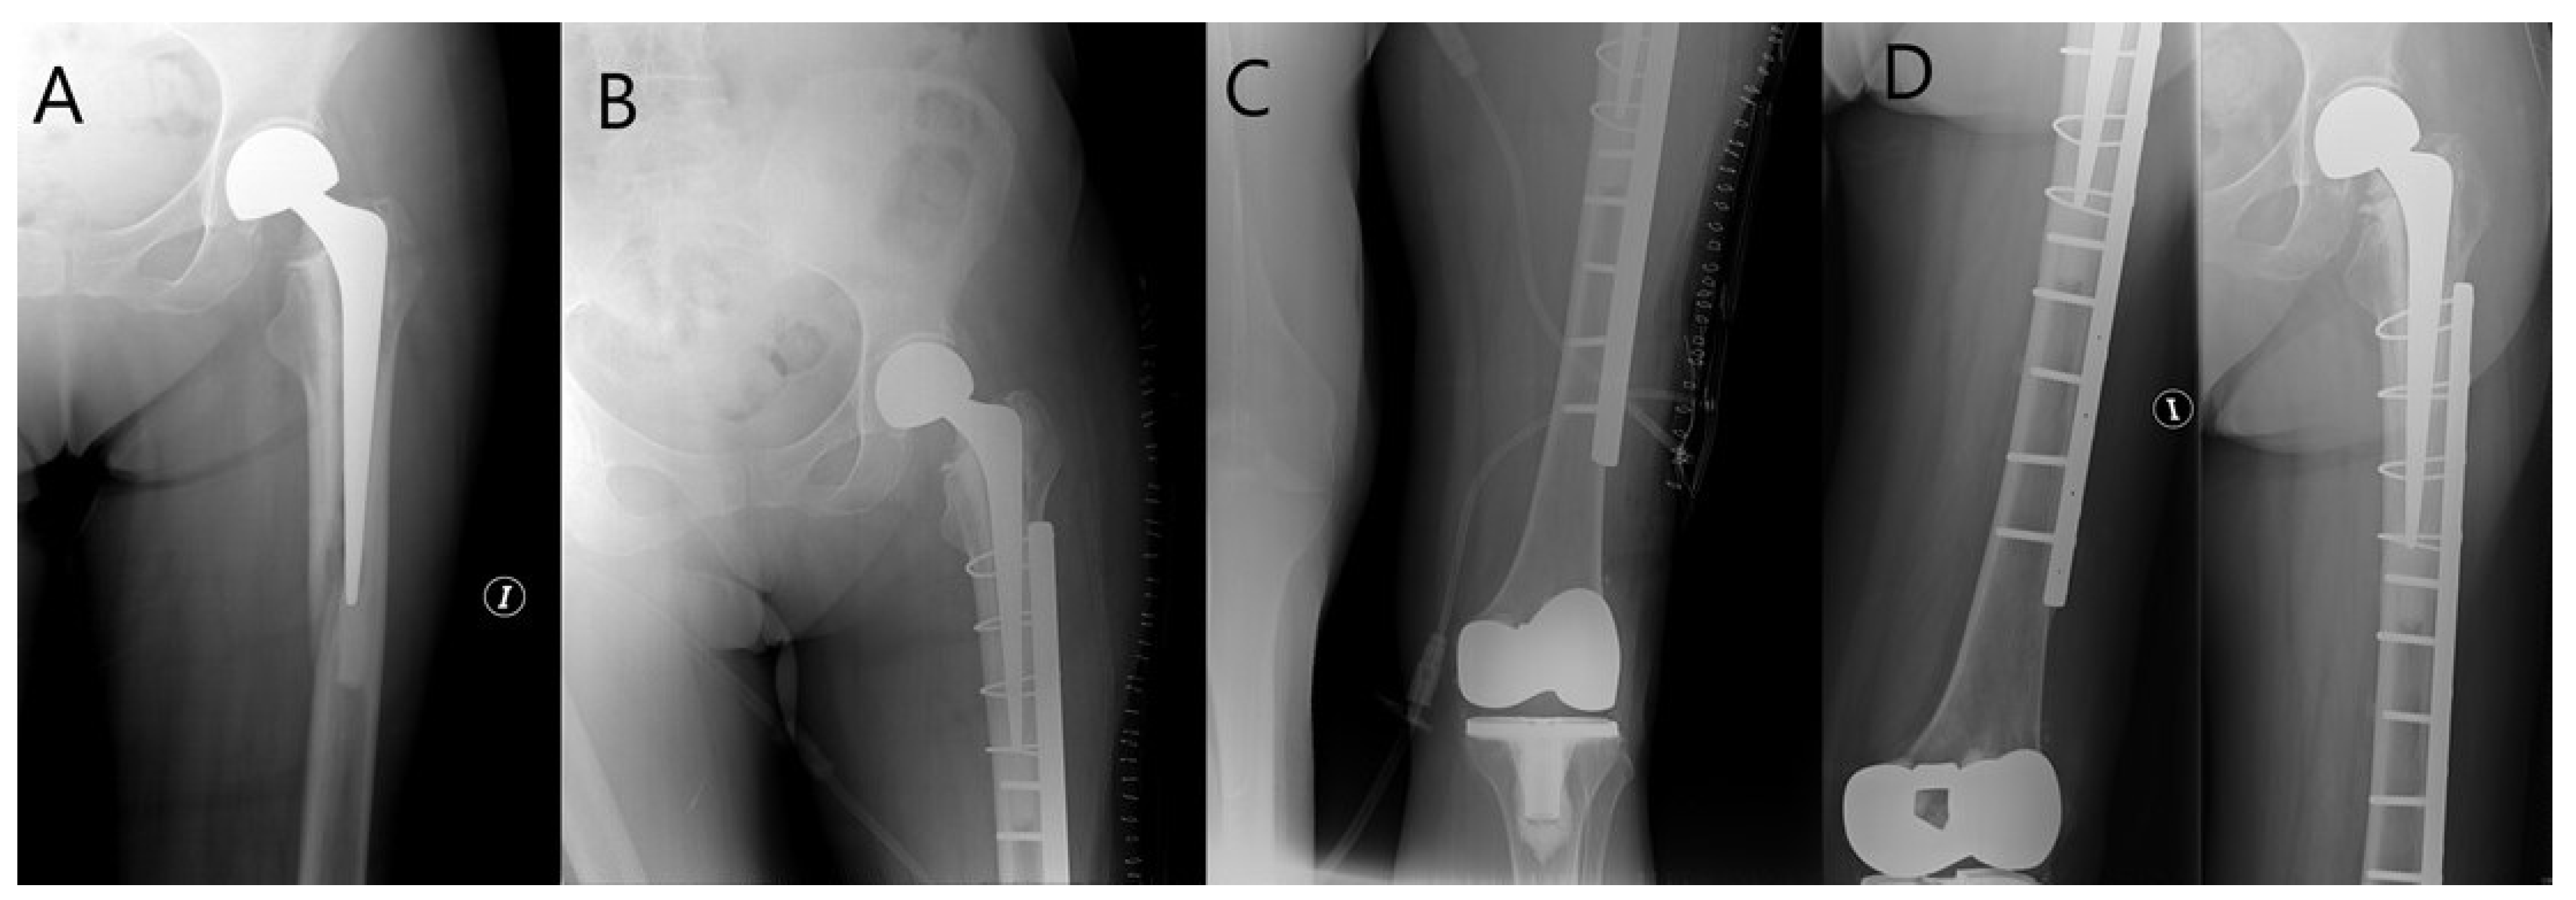

- González-Martín, D.; Pais-Brito, J.L.; González-Casamayor, S.; Guerra-Ferraz, A.; Ojeda-Jiménez, J.; Herrera-Pérez, M. New Sub-Classification of Vancouver B2 Periprosthetic Hip Fractures According to Fracture Pattern. Injury 2021. [Google Scholar] [CrossRef]